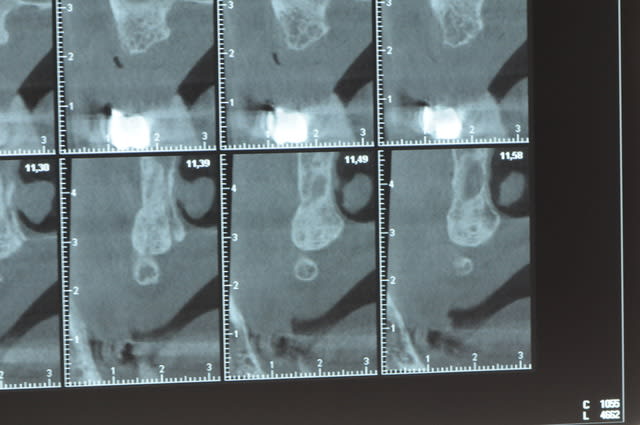

Une petite étude de ton cas D57

Les zones exploitables radiologiquement parlant:

Coupes implant

2,3 40100

4,96 35130 avec sinus lift mais difficile

5,25 35150

6,02 35130

6,78 35115 après réduction de hauteur de crête

7,26 35115 après réduction de hauteur de crête

8,51 35150

10,43 40115 ou 50115

11,10 40115

Ce qui nous fait 9 implants possible évidement avec un comblement de sinus on augmenterait encore les zones implantable mais ce n’est pas le but recherché, avec 8 (4+4) il doit être possible de faire une belle barre support de complet